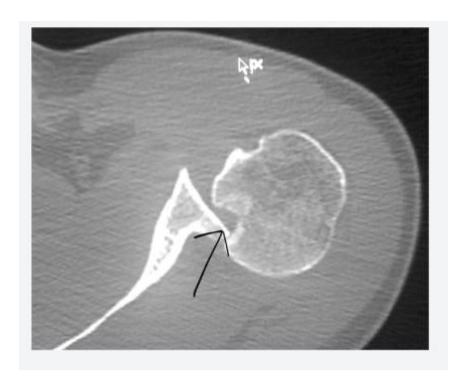

18-year-old male presented after sport injury and unable to do internal rotation of right shoulder. What is the name of the injury seen in the figure?

- Hill-Sachโs defect

- Hill-Sachs lesion

A case scenario about a male with anterior shoulder dislocation. What does the figure 1b show?

- Hill sachs lesion